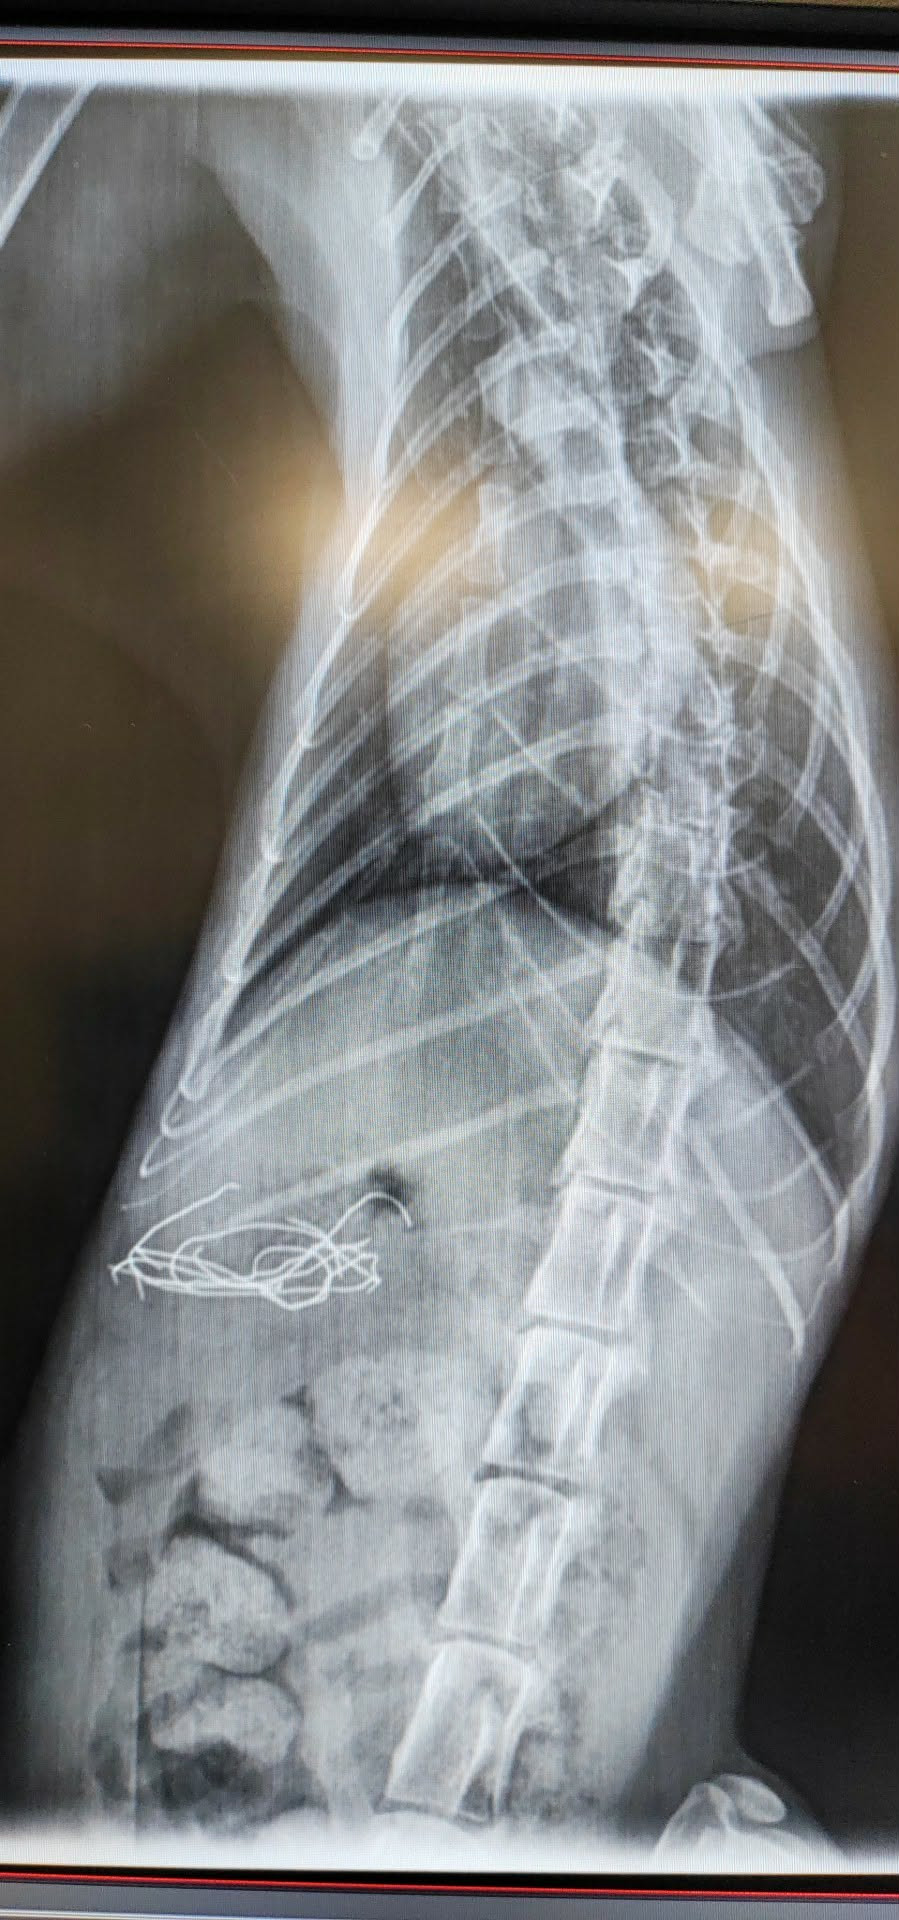

Test ukázal pozitivitu na panleukopenii. Kočičí mor. Kdo zná, ví… tohle je jako když přichází smrt s kosou. 😔

Neváhali jsme ani vteřinu. Hned jsme pro něj zajistili místo na infekčním oddělení kliniky. Tam teď Shadow bojuje o život. A my věříme, že to zvládne.

Denní pobyt na infekčním oddělení stojí 4000 Kč. Shadow tam pravděpodobně stráví nejméně 10 dní… to je 40 000 Kč.